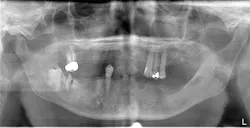

A healthy 72-year-old patient presented with failing dentition and maxillary and mandibular removable partial dentures (figures 5–7). After discussing treatment alternatives, it was decided to extract the remaining teeth and place four implants each in the maxilla and mandible to retain overdentures.

Figure 6: Pre-op panorex